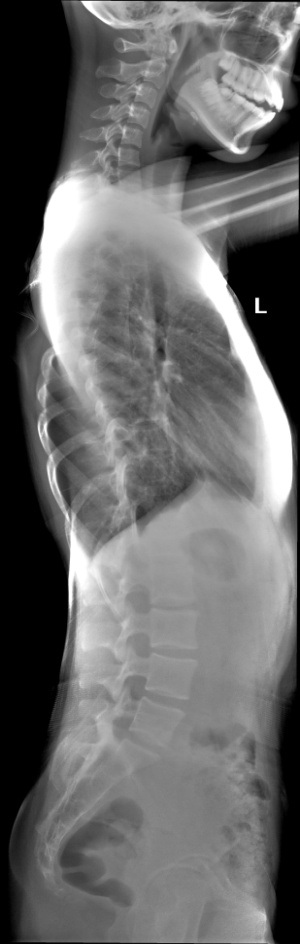

全脊柱X线片,大部分是由脊柱分段拍摄,然后运用拼接技术拼接而成。

体位设计: 站立位摄影时患者站立于拼接架上,背靠支架,双手扶住扶手,双下肢直立,双足稍微分开,保持身体静止, 双眼平视前方; 站立侧位摄影时患者站立于拼接架上,身体一侧靠近支架面板; 同样是,双手扶住扶手,双下肢直立,双足稍微分开,保持身体静止;

脊柱侧弯的金标准是X光,所以如果真的担心自己有脊柱侧弯的话,通过拍摄全脊柱X线 片,就可以明确诊断了。